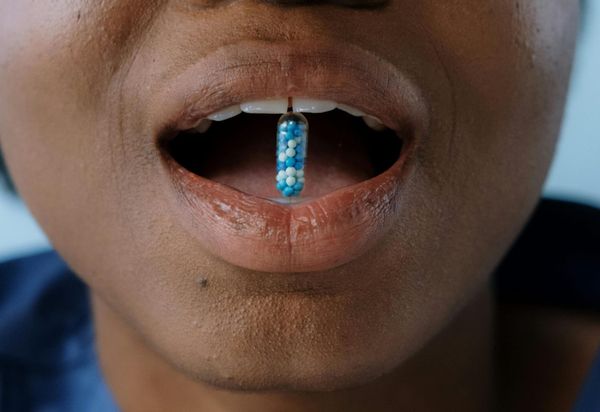

Why is a government agency selling small vials of human poop?

At-home gut microbiome tests are not as reliable as many would like them to be. A new standard from the US government’s National Institute of Standards and Technologies could finally change that.